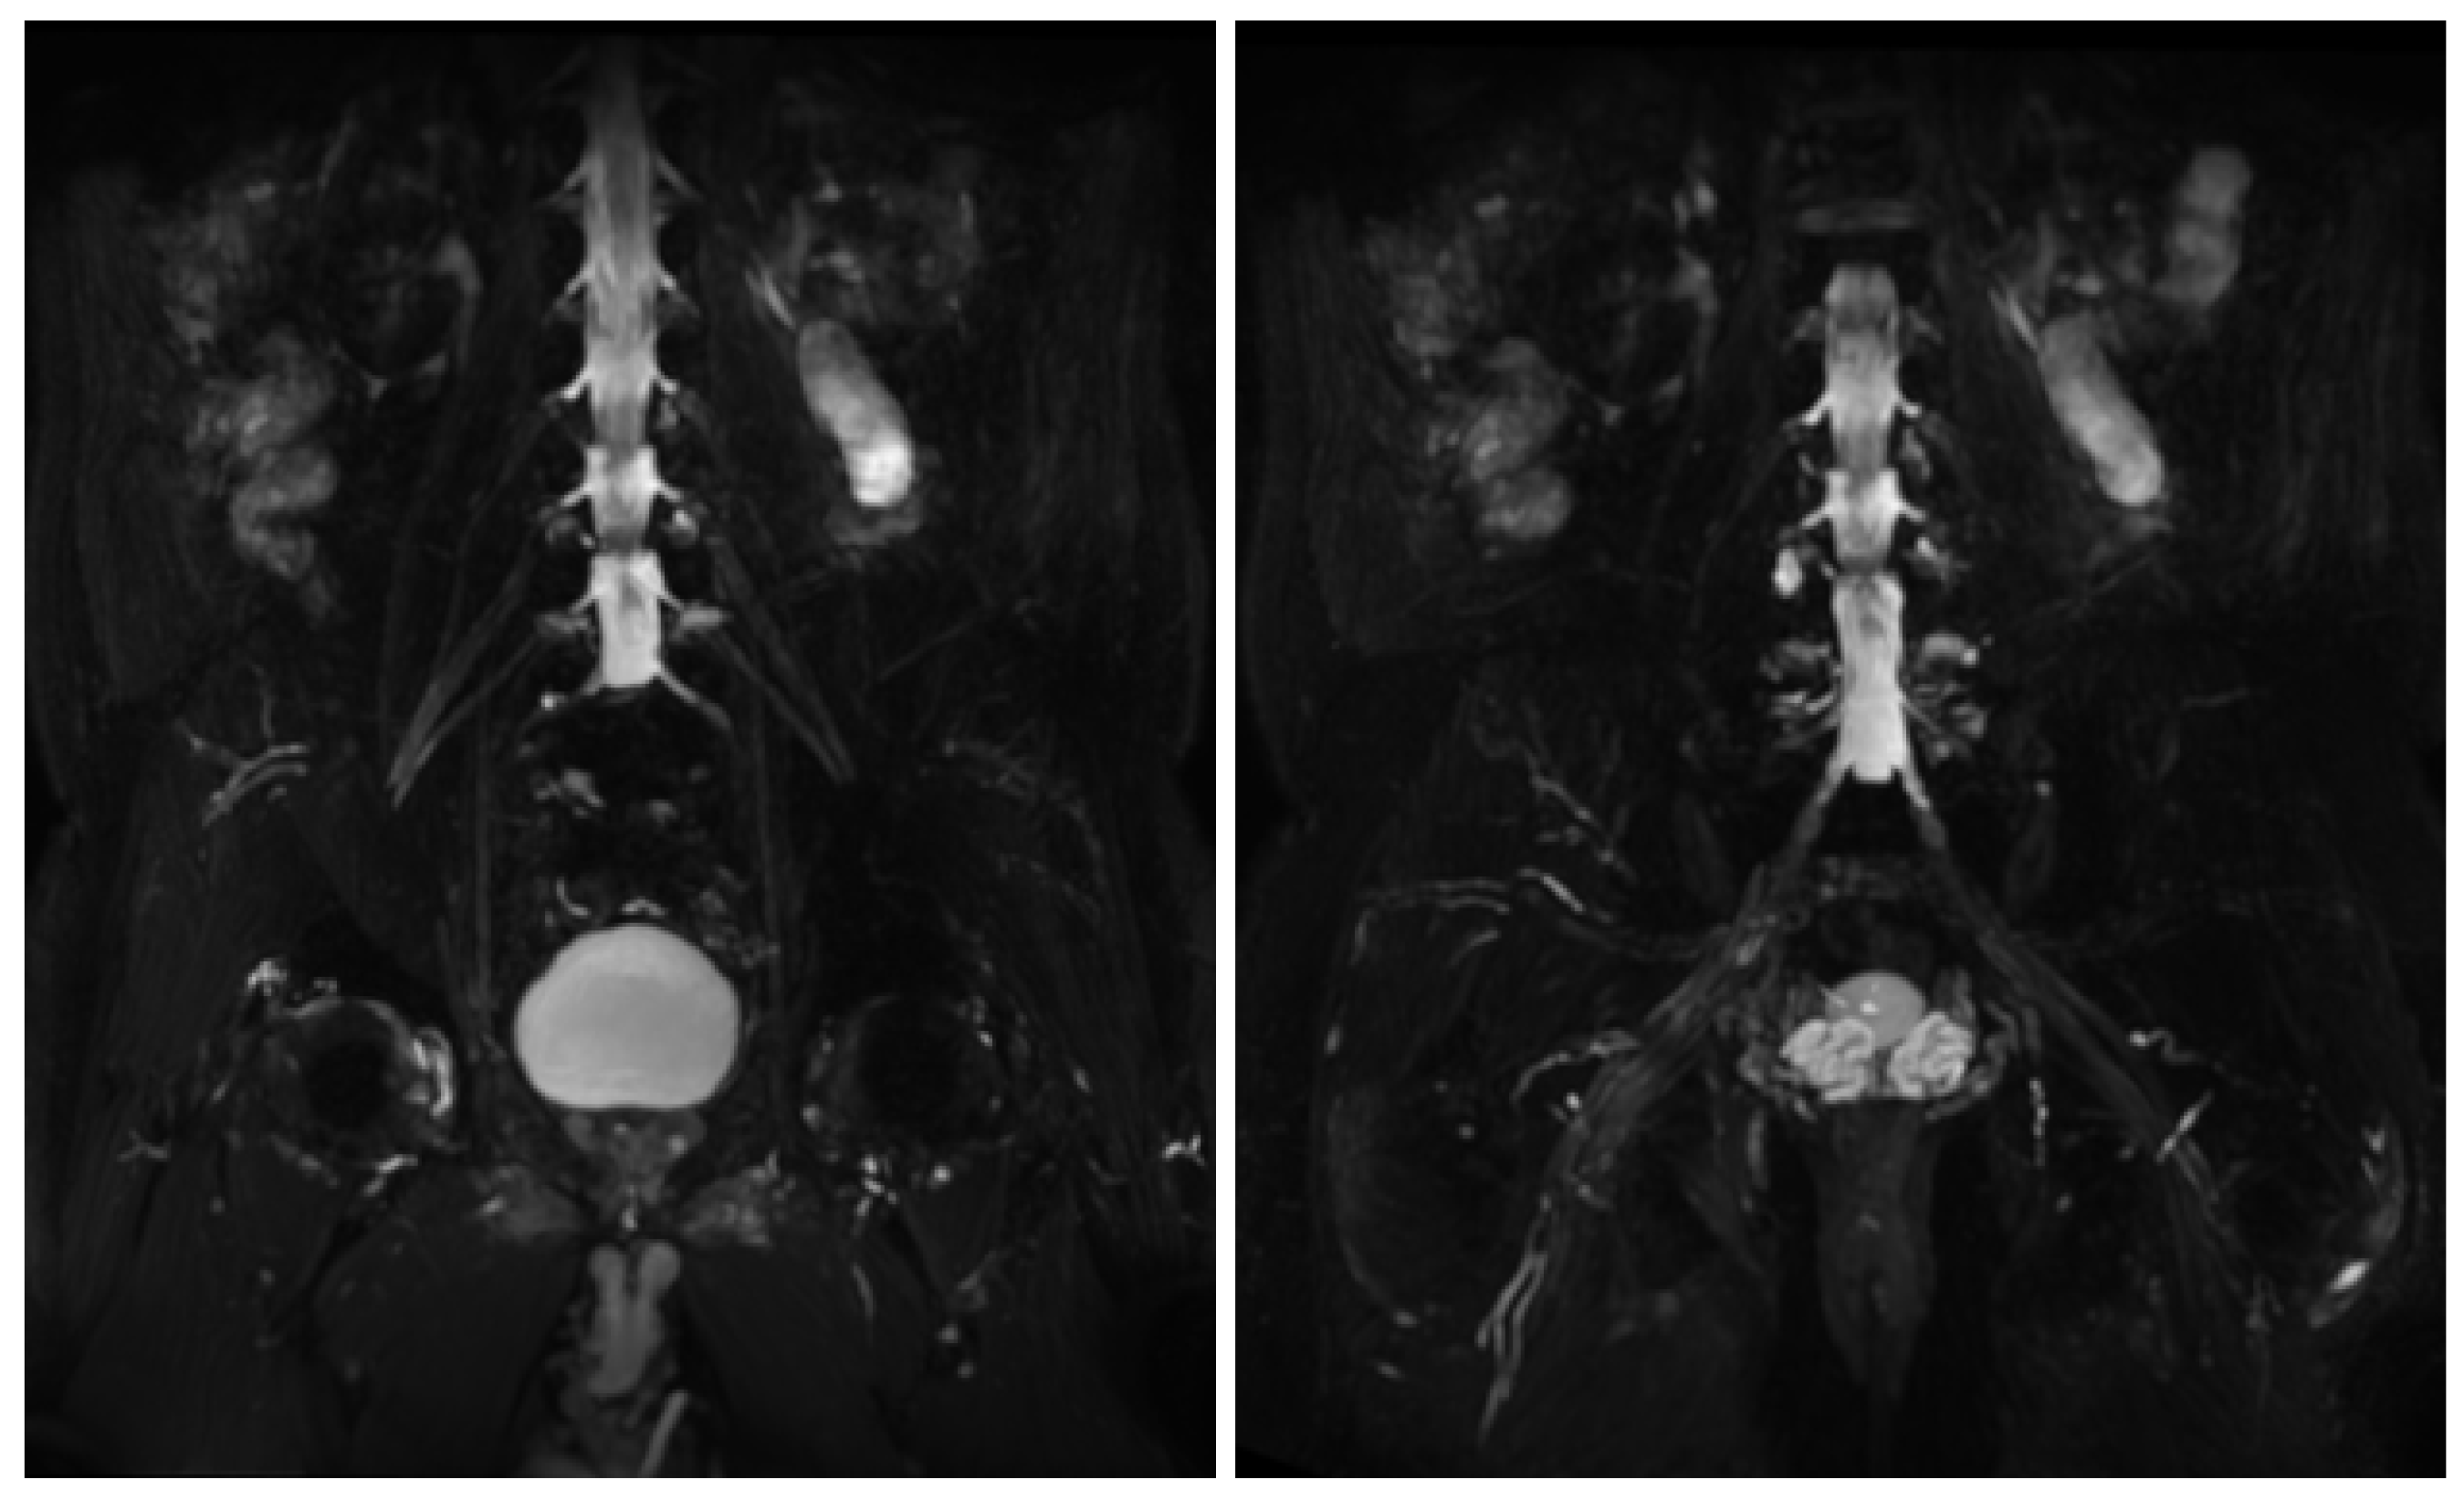

Figure 6.

MIP (Maximum Intensity Projection) reconstructions of the 3D cube nerve MR sequence of the lumbosacral plexus show regular size and signal intensity of lumbar and sacral roots.

Figure 7.

Axial 2D MR of sciatic nerve; on the left are the T1w images and on the right are the T2 STIR images. Bilateral and symmetrical sciatic nerve T2 enlargement and fascicular hyperintensity at the level of the gluteal region (thin arrows (B); CSA of sciatic nerve of 103 mm2 on the right; 90.1 mm2 on the left) and at the mid-thigh (thin arrows in (D,F)). Mixed, acute and chronic denervation of the muscles of the anterolateral compartment of the thigh with denervation edema (hyperintensity in STIR, arrowheads in (D,F)) and fat replacement (thick arrows in (C,E)). Mainly chronic denervation of the gluteal muscles (hyperintensity in T1w, thick arrows in (A)).